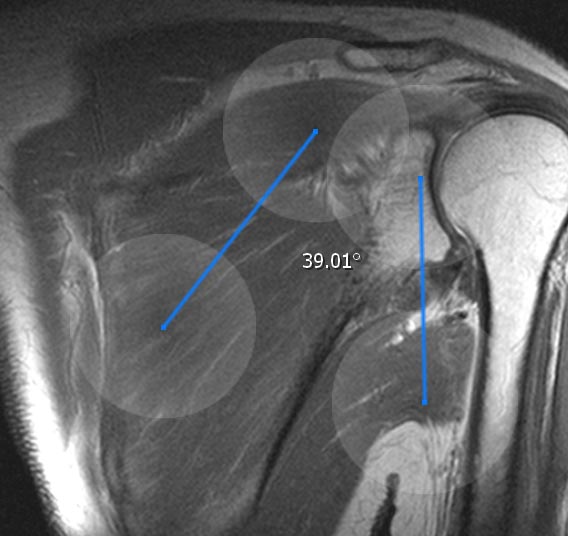

11.1.5. Angle tools

The angle tools allows you to create an angle in the current image slice. The angles lines are adjustable in their length and direction so that you can modify the angle by your needs. You can move the whole angle by tap and hold the intercept point. The angle can be deleted from the annotation menu.

Beside the normal angle tool there is the remote angle. While the normal angle is a real angle, the remote angle calculates the angle between two lines without a crossing point. Beside that, it can be used like the normal angle tool.